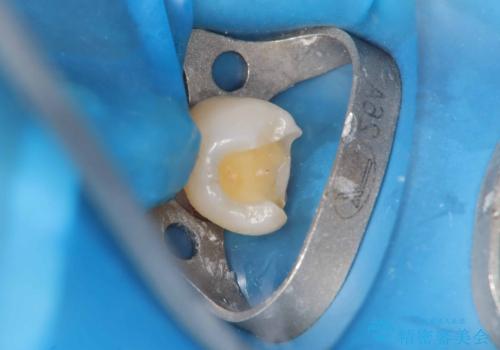

当院ではセラッミクインレーをつける時は必ずラバーダムを使用して付けます。

唾液と湿気はセラミックインレーの接着を阻害するのでラバーダムを使用しそれを防ぎます。